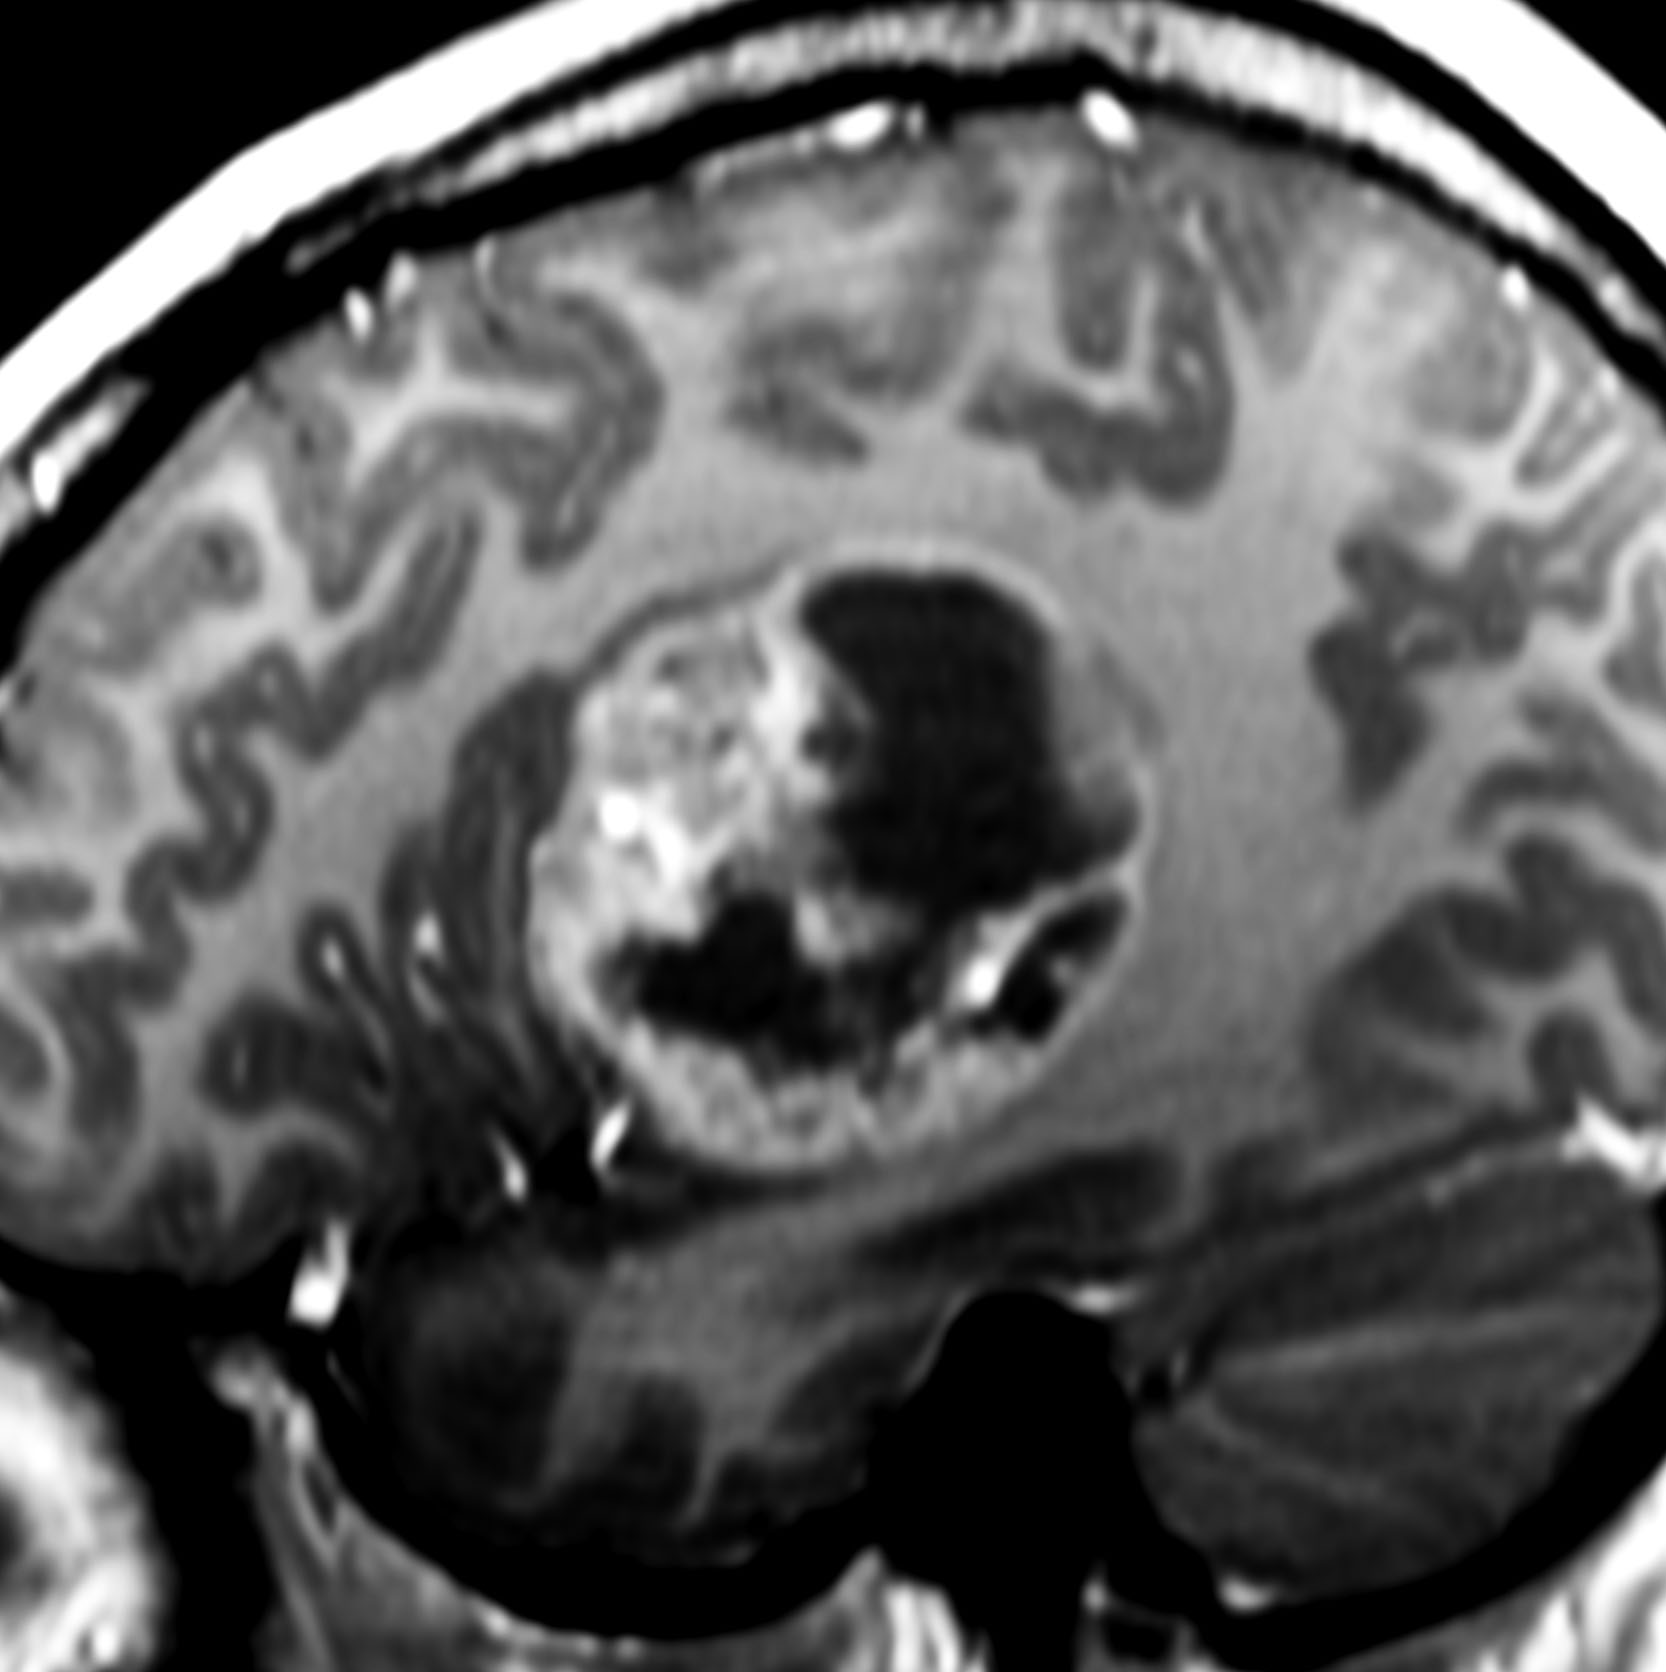

- 大脳表在性のものが多く,結節様でのう胞性と表現されます

- 腫瘍境界 demarcation が明瞭で浸潤像を示さないのが特徴です

- 半数以上に腫瘍内のう胞がみられ,multicystic bubbly appearanceと呼ばれます

- 腫瘍周囲がガドリニウムで強く増強さますが,heterogenous enhancementです

- まれに,腫瘍内出血によりのう胞内に二ボー fluid-fluid levelがみられます

境界明瞭な腫瘍で,腫瘍内にのう胞形成し,腫瘍実質は強くガドリニウム増強されます。これは深部ですが,脳表発生のものの方が多いです。他の小児悪性神経膠腫と画像では鑑別できません。退形成性上衣腫や旧来のPNETと呼称された悪性神経膠腫との画像類似性は強いです。